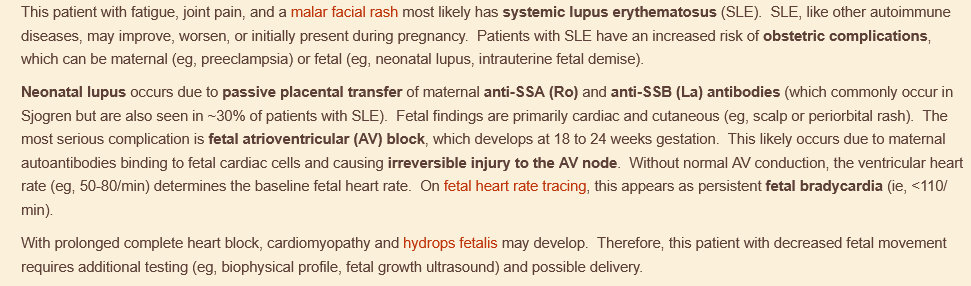

decreased fetal movement & nonpainful but regular contractions, no prenatal care. mother has fatigue, joint stiffness, and erythematous, confluent facial rash

fetal AV block due to mother’s lupus